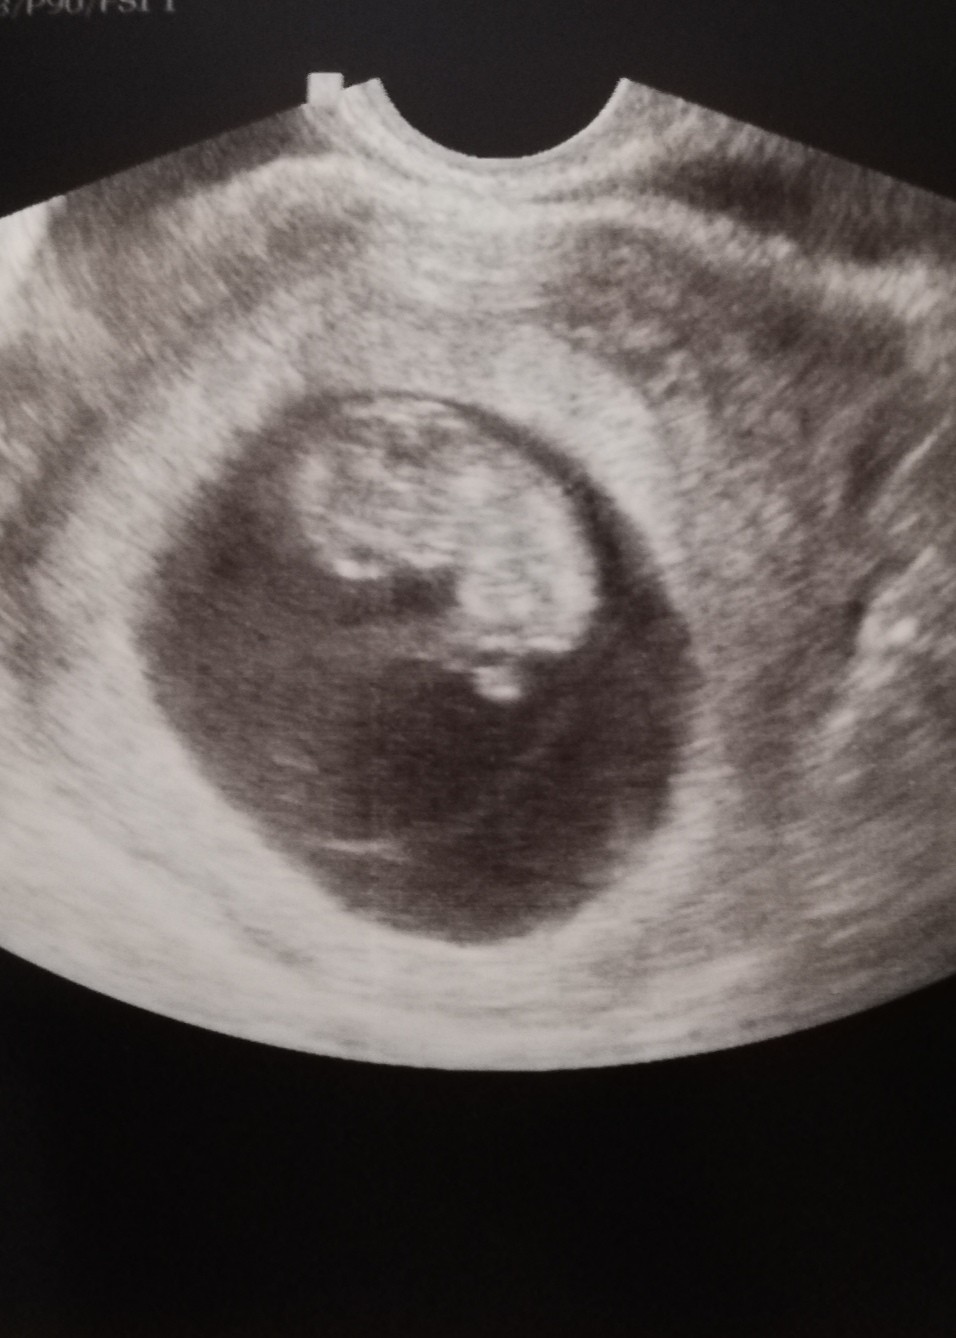

Ja również po wizycie, lekarka mówiła że wszystko jest ok. Ma już 2,39 cm. Ale niestety nie słyszałam serca ani nic Pani na ten temat nie mówiła. Mam się umówić na prenatalne na 8 marca :)

Załączniki

• IMG_20210210_212843.jpg

IMG_20210210_212843.jpg

158,4 KB · Wyświetleń: 85